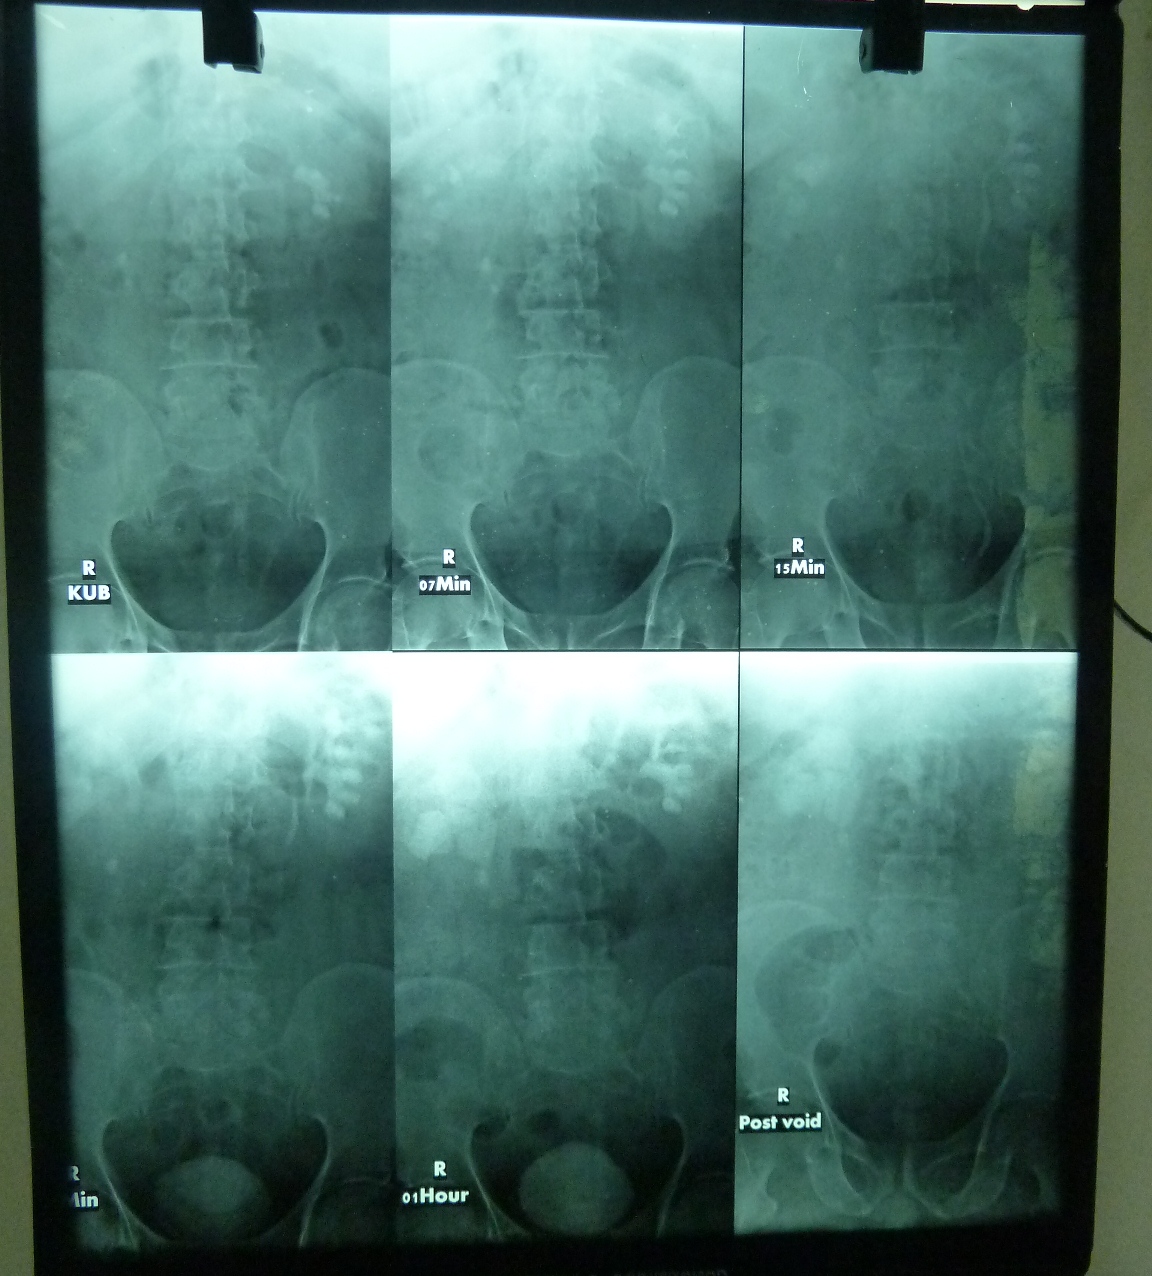

From www.wjgnet.com

Acute kidney injury and the compensation of kidney function after What Is A Partial Kidney Removal Called It is recommended whenever possible. partial nephrectomy is used to treat kidney cancer that has not spread to other tissue. Bilateral nephrectomy is the surgical removal of both kidneys. The goal is to remove the diseased or. a nephrectomy is a major surgery to remove all or part of your kidney. It is performed by a urologic surgeon.. What Is A Partial Kidney Removal Called.